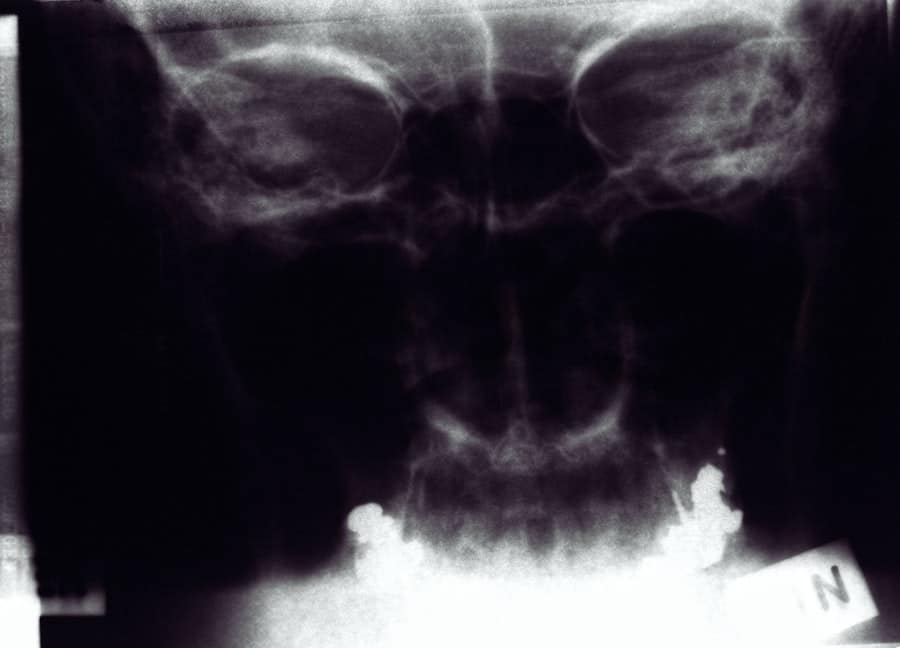

You will also have the chance to share your aesthetic goals, whether you want to refine the tip of your nose, reduce its size, or correct a deviated septum. Following this discussion, the surgeon will perform a physical examination of your nose and face. This assessment may involve taking photographs for reference and analysis.

The surgeon will evaluate the proportions of your facial features and how they relate to your nose. This step is crucial in developing a personalized surgical plan that enhances your overall appearance while maintaining harmony with your other features. By the end of the consultation, you should have a clearer understanding of what rhinoplasty can achieve for you and how it will be approached.